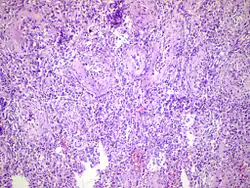

| Acute epididymitis with abundant fibrinopurulent exudate in the tubules. | |